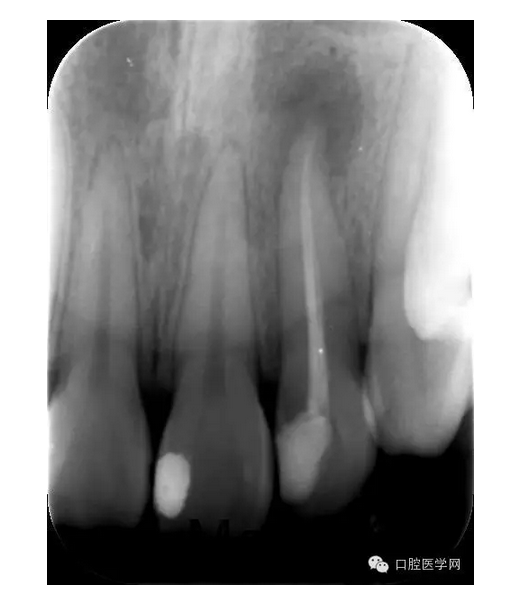

X線片:示22已行根管治療,治療不完善,根尖區(qū)可見(jiàn)約0.5*0.5mm密度減低區(qū),牙周膜影略增寬。